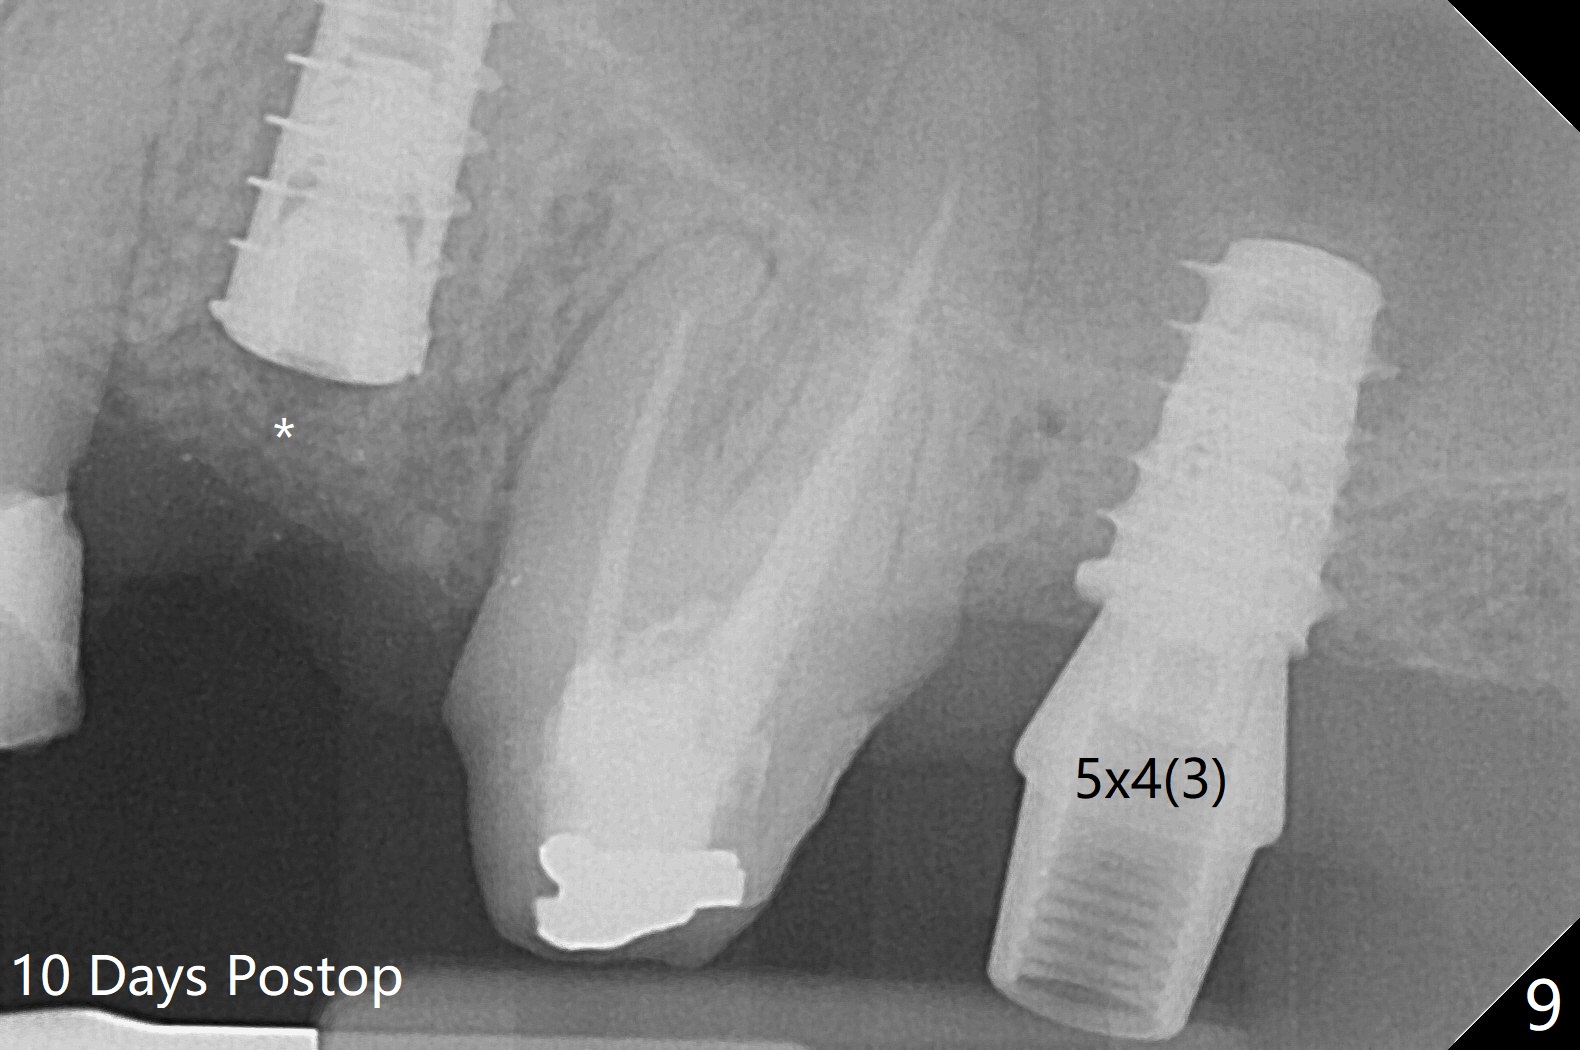

The patient with the anterior cross bite at the left lateral and canine and incipient Class V caries returns to clinic for #13 residual root extraction (Fig.1,2). There is no quality root structure (Fig.2) or space (Fig.3) for socket sheath. Two amalgam carriers of Vanilla is inserted and pushed by the 4x11 mm dummy implant for sinus lift (Fig.4 *). When the same sized final implant (4x11 mm) is placed, a 5.5 mm bone profile drill is used to trim the proximal crests (Fig.5 * sticky bone packed in the buccal and palatal gaps). In fact the implant turns when a 4.5x4(3) mm pair abutment is tightened. The implant is backed up; with a healing screw, sticky bone is placed (Fig.6 *) and then covered with a piece of PRF and a part of GEM cap. The wound is sutured with 4-0 PGA; periodontal dressing is applied. The implant is somewhat over-seated without the bone graft covering the apical end of the implant (Fig.7, as compared to Fig.4). A 4.5 mm implant should be placed. The GEM Cap appears to be absent 9 days postop, while the periodontal dressing dislodged in 1 week (Fig.8). It appears that the existing abutment at #15 is incompletely seated (Fig.3, 5.5x4(2) mm). After use of 5.5 and 6.0 mm bone profile drills, a 5x4(3) mm abutment is placed with 35 Ncm torque. In fact the bone graft coronal to the implant remains (Fig.9 *) in spite of apparent loss of the overlying PRF and GEM cap (Fig.8). After use of a 4.6 mm profile drill, a 5.5x3 mm healing abutment is placed 4.5 months postop (Fig.10). Without a provisional at #13 for ~ 4 months, there is a gap between crowns at #14 and 15 (not shown due to angulation). Impression is taken for #13 crown fabrication 5.5 months postop and for #15 crown repair (addition of porcelain for the mesial contact, Fig.11). It appears critical for a provisional to maintain the position of the neighboring tooth.